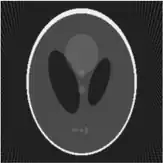

If a function represents an unknown density, then the Radon transform represents the projection data obtained as the output of a tomographic scan. Hence the inverse of the Radon transform can be used to reconstruct the original density from the projection data, and thus it forms the mathematical underpinning for tomographic reconstruction, also known as iterative reconstruction.

Iterative reconstruction methods

Compared with the Filtered Back-projection method, iterative reconstruction costs large computation time, limiting its practical use. However, due to the ill-posedness of Radon Inversion, the Filtered Back-projection method may be infeasible in the presence of discontinuity or noise. Iterative reconstruction methods (e.g. iterative Sparse Asymptotic Minimum Variance[10]) could provide metal artefact reduction, noise and dose reduction for the reconstructed result that attract much research interest around the world.

Thus in an image processing context the original image can be recovered from the 'sinogram' data by applying a ramp filter (in the variable) and then back-projecting. As the filtering step can be performed efficiently (for example using digital signal processing techniques) and the back projection step is simply an accumulation of values in the pixels of the image, this results in a highly efficient, and hence widely used, algorithm. Explicitly, the inversion formula obtained by the latter method is:[4]